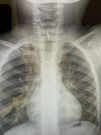

Radio de l'enfant : la trachée est bouchée par un os